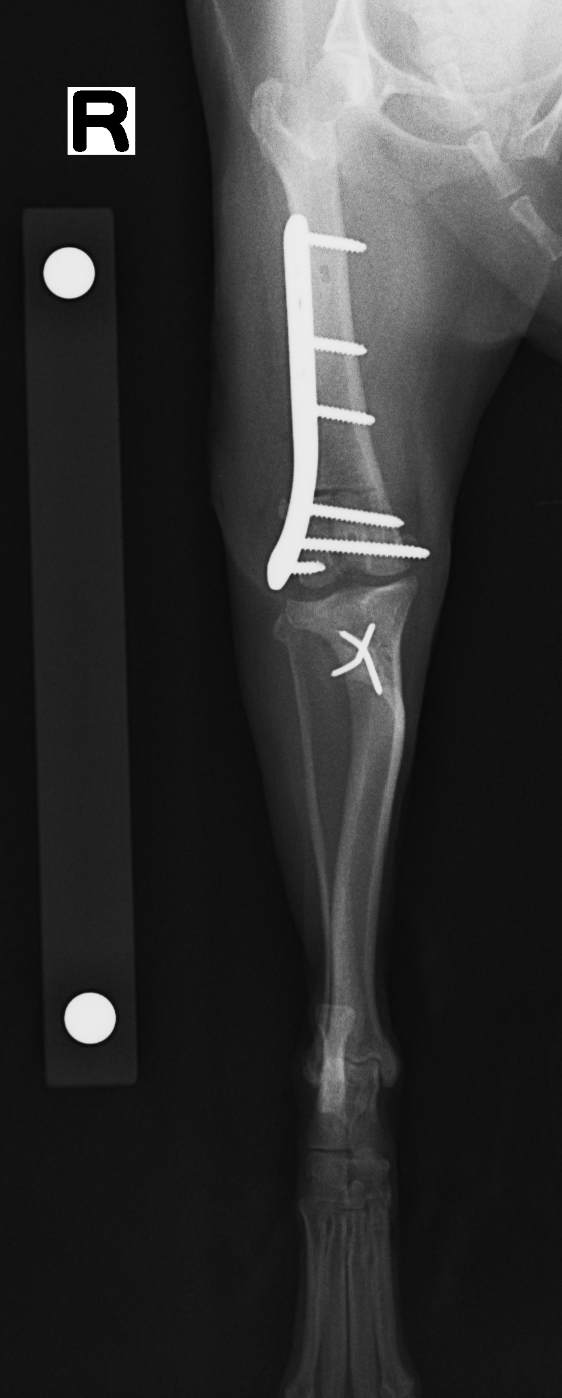

重度の膝蓋骨内方脱臼

重度な膝蓋骨内方脱臼になってくると、成長期段階で大腿骨や脛骨に大きな変形が起きてきます。 大腿骨遠位の内反と脛骨の内旋は多く認められる変形である。 一般的に多く実施される脛骨粗面転位術(TTT)もこの脛骨の内旋に対する矯正骨切術である。 大腿骨に関しては、あまり行われていないが変形が強い場合、変形を矯正するため、矯正骨切術が行われる。 大腿骨矯正骨切術は、aLFDA→95±10°の範囲で適応と考え、前捻角(15-25° 小型犬と大型犬でやや異なる)もJIGを利用することで同時に矯正できる。前捻角はCTで測定すると確実で、当院ではそうしている。 大腿骨の矯正骨切術に使用する大腿骨プレートは、各社様々なものが使用できる。コンディラープレートを使用される方もいらっしゃいます。当院ではMOVORA社の大腿骨プレートを使用。